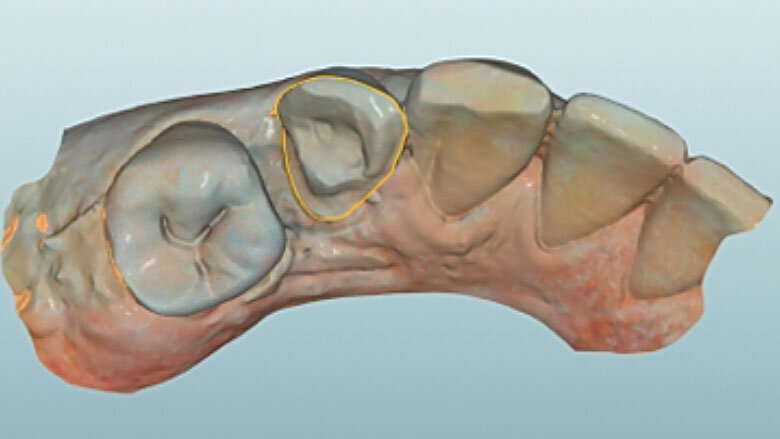

Fig. 7. Durante el diseño de la restauración se respetaron los grosores de capa mínimos.

Fig. 8. Vista oclusal de la endocorona virtual en el software CAD.

Fig. 9. Vista lingual del diseño.

CAM y acabado

Acto seguido se diseñó digitalmente la endocorona y se confeccionó a partir de VITABLOCS Mark II mediante la unidad de fresado MyCrown Mill (FONA Dental, Bratislava, Eslovaquia). Tras la separación del conector se llevó a cabo la prueba en boca de la restauración y a continuación se realizó su acabado cuidadoso con un diamante fino. Posteriormente se procedió a la caracterización de las fosas con VITA AKZENT Plus EFFECT STAINS (ES06, rojo óxido) y al glaseado final. Dado que una unión adhesiva fiable a la sustancia dental es un factor clave para el éxito clínico a largo plazo, se colocó un dique de goma para garantizar la ausencia de contaminación y la sequedad absoluta.